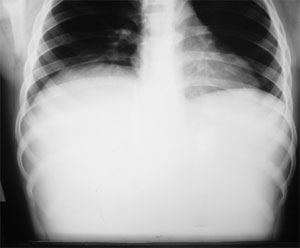

Liver & spleen scan by

99m-Tc phytate:

Angiography multiple

smallzones

with high blood flow

detected.

Static phase

demonstrated

a hugely enlarged liver

which was

occupied by a loculated

mass with

no uptake of

radiotracer.

Impression:

Hepatomegaly with a huge space-occupying lesion

Tc 99m-RBC scan:

Liver is occupied by a very

huge mass which

revealed gradual accumulation

of RBC-labeled radiotracer.

Impression: Scan is in favor

of a

very huge and loculated

hemangioma

with

probable AV malformation

inside the lesion.